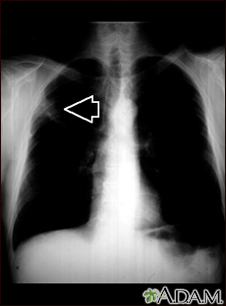

Lung mass, right upper lung - chest x-ray